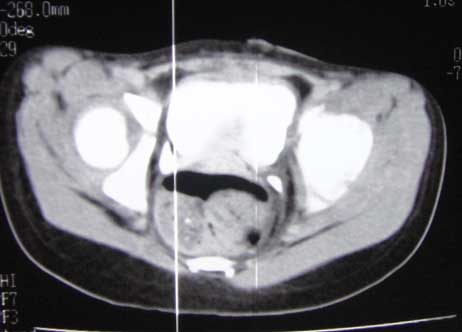

*CT scanner:

Hình ảnh CT cho thấy thương tổn đốt sống

- Cột sống từ L4 trở xuống cùng cụt hở gai sau kèm theo khiếm khuyết mảnh bên (P) nhiều hơn bên (T).

- Khối phì đại mô với tỷ trọng mỡ trong khoang ngoài màng cứng ống sống đoạn hở gai ( từ bờ dưới L3) phát triển liên tục với mô dưới da vùng cùng cụt.

- Nón tủy vị trí thấp tương ứng L3-L4. Dây tận cùng dày và ngắn, dính ra sau với khối mỡ qua chổ hở gai của S1.

- Thận 2 bên: kích thước, cấu trúc và ngấm thuốc bình thường, niệu quản 2 bên không giãn.

- Bàng quang thành dày lan tỏa, chưa thấy hình ảnh giả túi thừa ( dò qua đường dẫn lưu bàng quang trước đây).